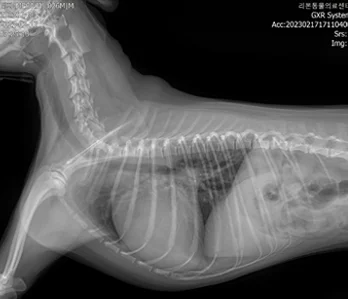

• X-RAY

내부 장기나 조직의 이상은 외부에서 관찰할 수 없기 때문에, 이를 정확히 파악하기 위해서는 영상진단이 꼭 필요합니다. 특히 반려동물의 경우, 어디가 불편한지 직접적으로 표현할 수 없기 때문에

영상 장비를 통한 꼼꼼한 진단이 더욱 중요합니다. 보호자의 눈에는 단순한 이상으로 보일 수 있는 증상도, 영상검사를 통해 내부 장기의 문제로 확인되는 경우가 많습니다.

영상의학과는 X-ray, 초음파, CT, MRI 등 다양한 첨단 장비를 활용하여 동물의 내부 상태를 영상으로 표현하고, 이를 기반으로 정확한 진단과 치료 방향을 제시하는 역할을 합니다.

• X-RAY 케이스 수 : 3만건 이상

다년간 다수의 케이스를 다룬 영상진단 전공 수의사들이 직접 판독 및 진단하며, 정확한 진단은 곧 효과적인 치료로 이어집니다.